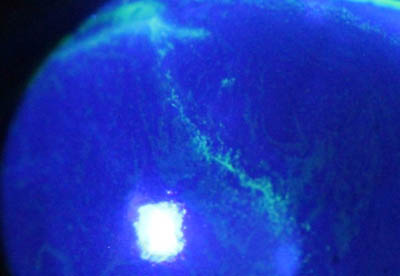

Perineuritis

No tienen los bulbos terminales de las dendritas del Herpes Simple

Formación de lineas epiteliales elevadas que pueden dar la imagen de Seudodendrítas + Perineuritis

Perineuritis